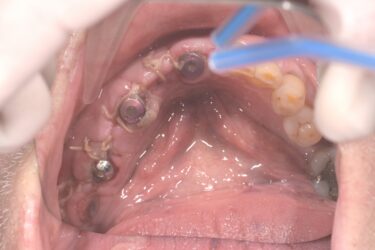

Hi I have an implant bridge case to restore. Pt is in his 80s. I have just been restoring single units before this and would love some help/advice about how to proceed. The initial idea was just to scan, which I’m comfortable doing. But I have learned that the scanner may not be so accurate for larger cases like this. I will order a special tray first of all.

@bishaya thanks. If I were to scan, would u recommend splinting the scan bodies. Not sure about the exact restorative space but we have done a wax up for the surgical guide and it’s not deficient. Although I should start measuring it from now on. I was just going to go titanium base then zirconia. Is that what u would do?